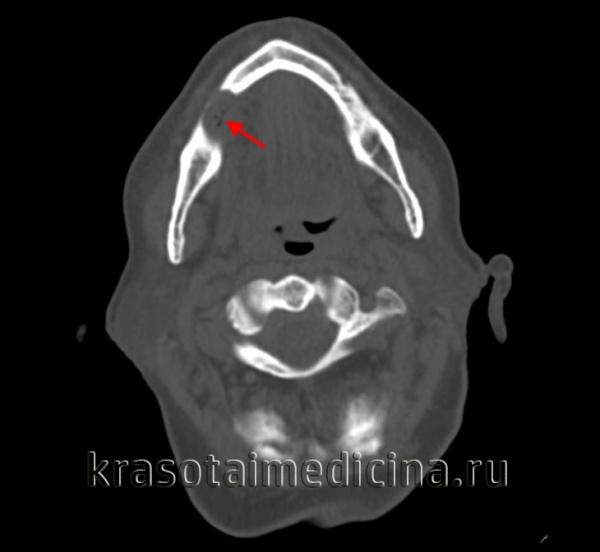

(Справа) КТ с КУ в аксиальной проекции, этот же пациент. В области правого отверстия нижней челюсти определяется накапливающая контраст опухоль. В жевательном пространстве видны участки аномального накопления контраста вдоль волокон нижнечелюстного нерва.